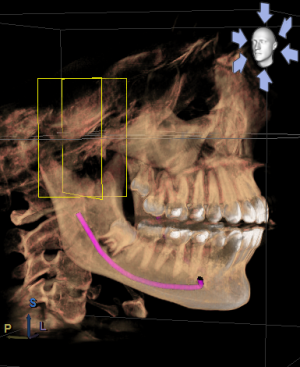

Здравствуйте! У моей дочери 16ти лет проблема с ВНЧС. При ношении брекетов ей вытягивали нижнюю челюсть, выравнивали прикус и зубы , в частности - клыки выпирающие выравнивали. А через 1,5 года после снятия в одно прекрасное утро не смогла открыть рот. Нам советовали делать лазер, становилось легче. Так было 2 раза. А теперь по утрам, если спит на правой щеке, то челюсть правую заклинивает. Голова сильно болит в висках. Связано ли это с брекетами или другая причина может быть? Читая в интернете об этой проблеме, поняла, что это дело очень тонкое и непростое, испортить жизнь ребенку можно запросто. А еще советуют мануального терапевта. Куда пойти ? У нас есть КТ в 3Д и еще нас на МРТ направили. Может ли мануальный терапевт решить эти проблемы? Знакомый стоматолог сказал, что если челюсть поправят, то прикус может нарушится. А мануальный говорит - приходите - все исправим, даже снимков ему не надо. .Теперь хочу выяснить у специалистов, как все таки поступить. К кому пойти сначала. Очень Вам буду благодарна за совет. Вот еще сделала скриншоты томографии